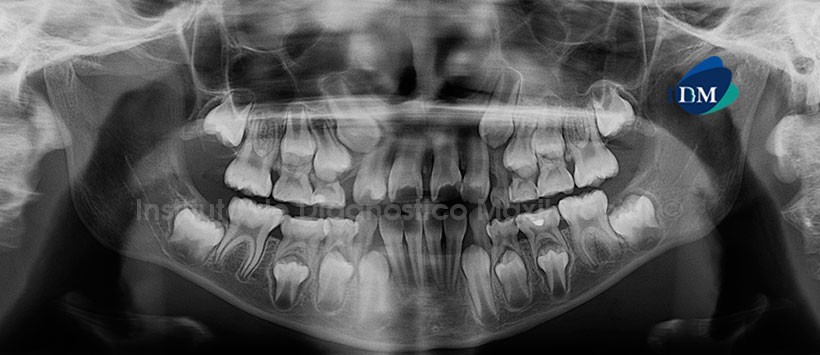

Paciente femenino de 9 años de edad que es referida por presentar un aumento de volumen en el paladar duro, a nivel del sector anterior del maxilar superior izquierdo, y que presenta ulceraciones en la mencionada región. La radiografía panorámica nos muestra múltiples lesiones cariosas; así como, restauraciones coronarias con lesiones cariosas recidivantes. Por otro lado, la pieza 53 está ausente. No se evidencia cambios radiográficos en la zona de interés (Fig. 1).